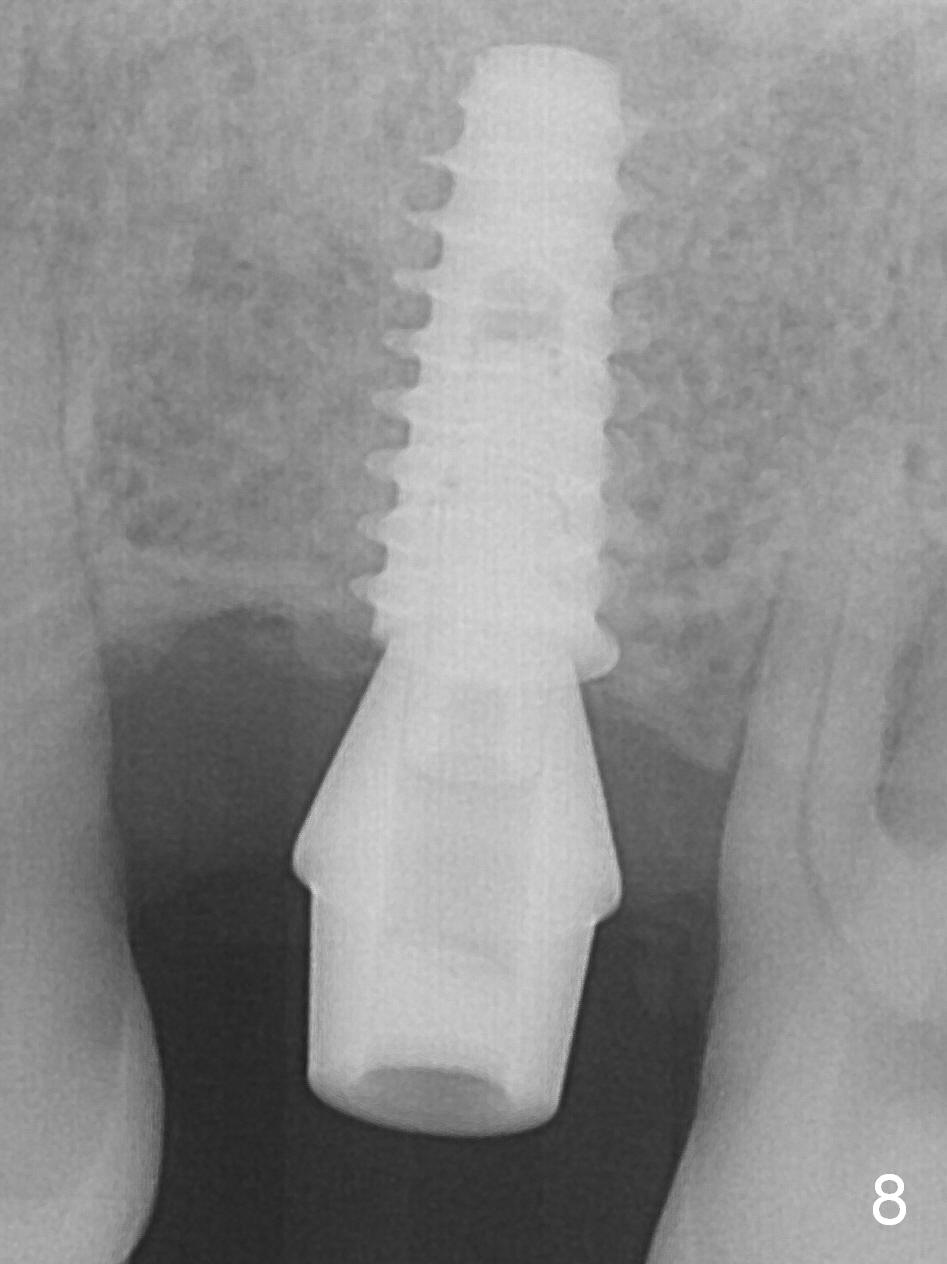

Magic split is designed to test bone density after incision (Fig.1). Since it is sharp and blade-shaped (Fig.2), it is used as a scalpel to penetrate the mucosa at the crest of #14 and tapped in for ~ 7 mm from the gingival margin. The bone density is moderate. Osteotomy is initiated with 1.6 mm pilot drill for 13 mm (Fig.3,4 (red line: the lower border of the sinus floor) and increased by Magic Expanders (ME) and Magic Drills until 4.5x13 mm. A 5x11 mm dummy implant is placed (Fig.5). After reusing ME 3.8 mm for 13 mm at the palatal gingival margin (which is more apical than the buccal one by ~2 mm), a definitive IBS implant (5x11 mm) is placed (Fig.6). Later the implant is turned 4 more times. Without an incision, there is no hemorrhage when a 6x4(4) mm Hexa abutment is placed (Fig.7 (palatal view) A). As a routine, an immediate provisional is fabricated with occlusal clearance. The implant/crown ratio is less favorable. Restore more than 4 months. In fact, the patient returns for crown 4 months postop. The implant appears to have osteointegrated (Fig.8).

Return to Upper Arch Molar Molar Immediate Implant, #7,18,19,30, 1st Year Course 1 2 Xin Wei, DDS, PhD, MS 1st edition 11/06/2016, last revision 10/24/2018